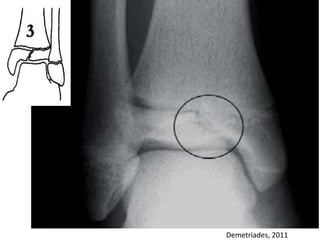

TNA

Fratura metafisária

proximal com elevação

perióstica, secundária

ao hematoma

perióstico.

Murray, 2008

TNA Fratura metafisária proximal comelevação perióstica, secundária ao hematoma perióstico. Murray, 2008